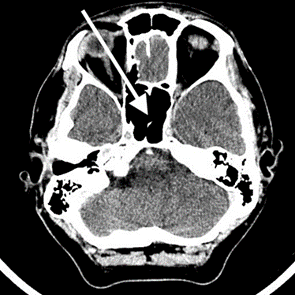

Co jest przyczyną artefaktu widocznego na obrazie MR?

Ilustracja do pytania 4

A. Zjawisko zaniku sygnału.

B. Ruch narządu lub pacjenta.

C. Zjawisko zawijania fazy.

D. Pulsacyjny przepływ krwi.